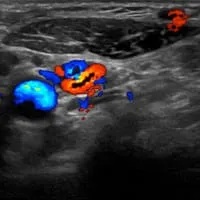

Ultrasound is performed without any radiation, and can demonstrate blood flow in the arteries in real time, allowing dynamic movement of the arms during the examination. However, bones create severe blind spots, limiting assessment of bony compression of arteries. Ultrasound is also quite limited for viewing fibrous bands and muscle anomalies.